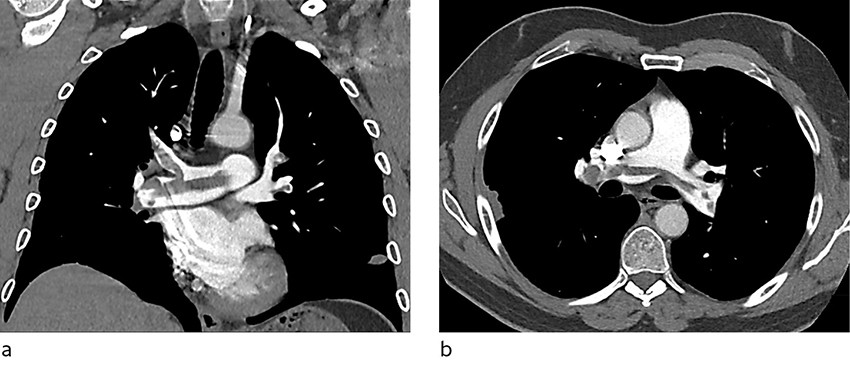

Enoksaparin (Klexane) 1 mg/kg ble gitt subkutant × 2. Pasienten ble lagt på telemetriovervåking, og CT av lungearterier ble bestilt til dagen etter. Denne avdekket en omfattende sadeltrombe samt bilaterale segmentale lungeemboluser (figur 1). Pasienten ble derfor flyttet til medisinsk intermediær avdeling for tett overvåking av sirkulasjonsstatus. Ekkokardiografi påviste en trombe i pulmonalarterien, lett dilatert høyre ventrikkel og avflatning av det interventrikulære septum. Estimert systolisk lungearterietrykk var 55 mm Hg (< 36).